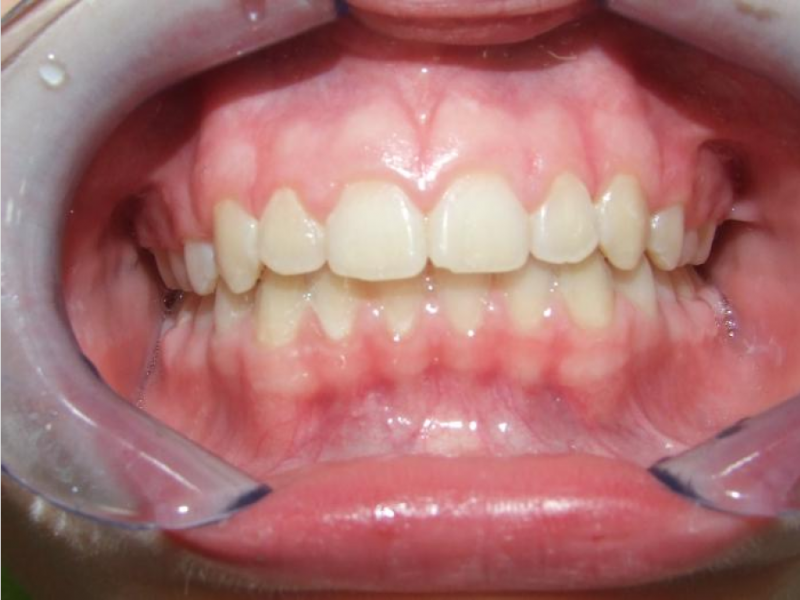

eindfoto

Beschrijving

Leeftijd bij aanvang: 10 jaar

Bonded Hyrax + volledig vast onderkaak

Volledig vast bovenkaak + expander

Wrap + c-c bar onderkaak

Leeftijd bij afname: 12 jaar